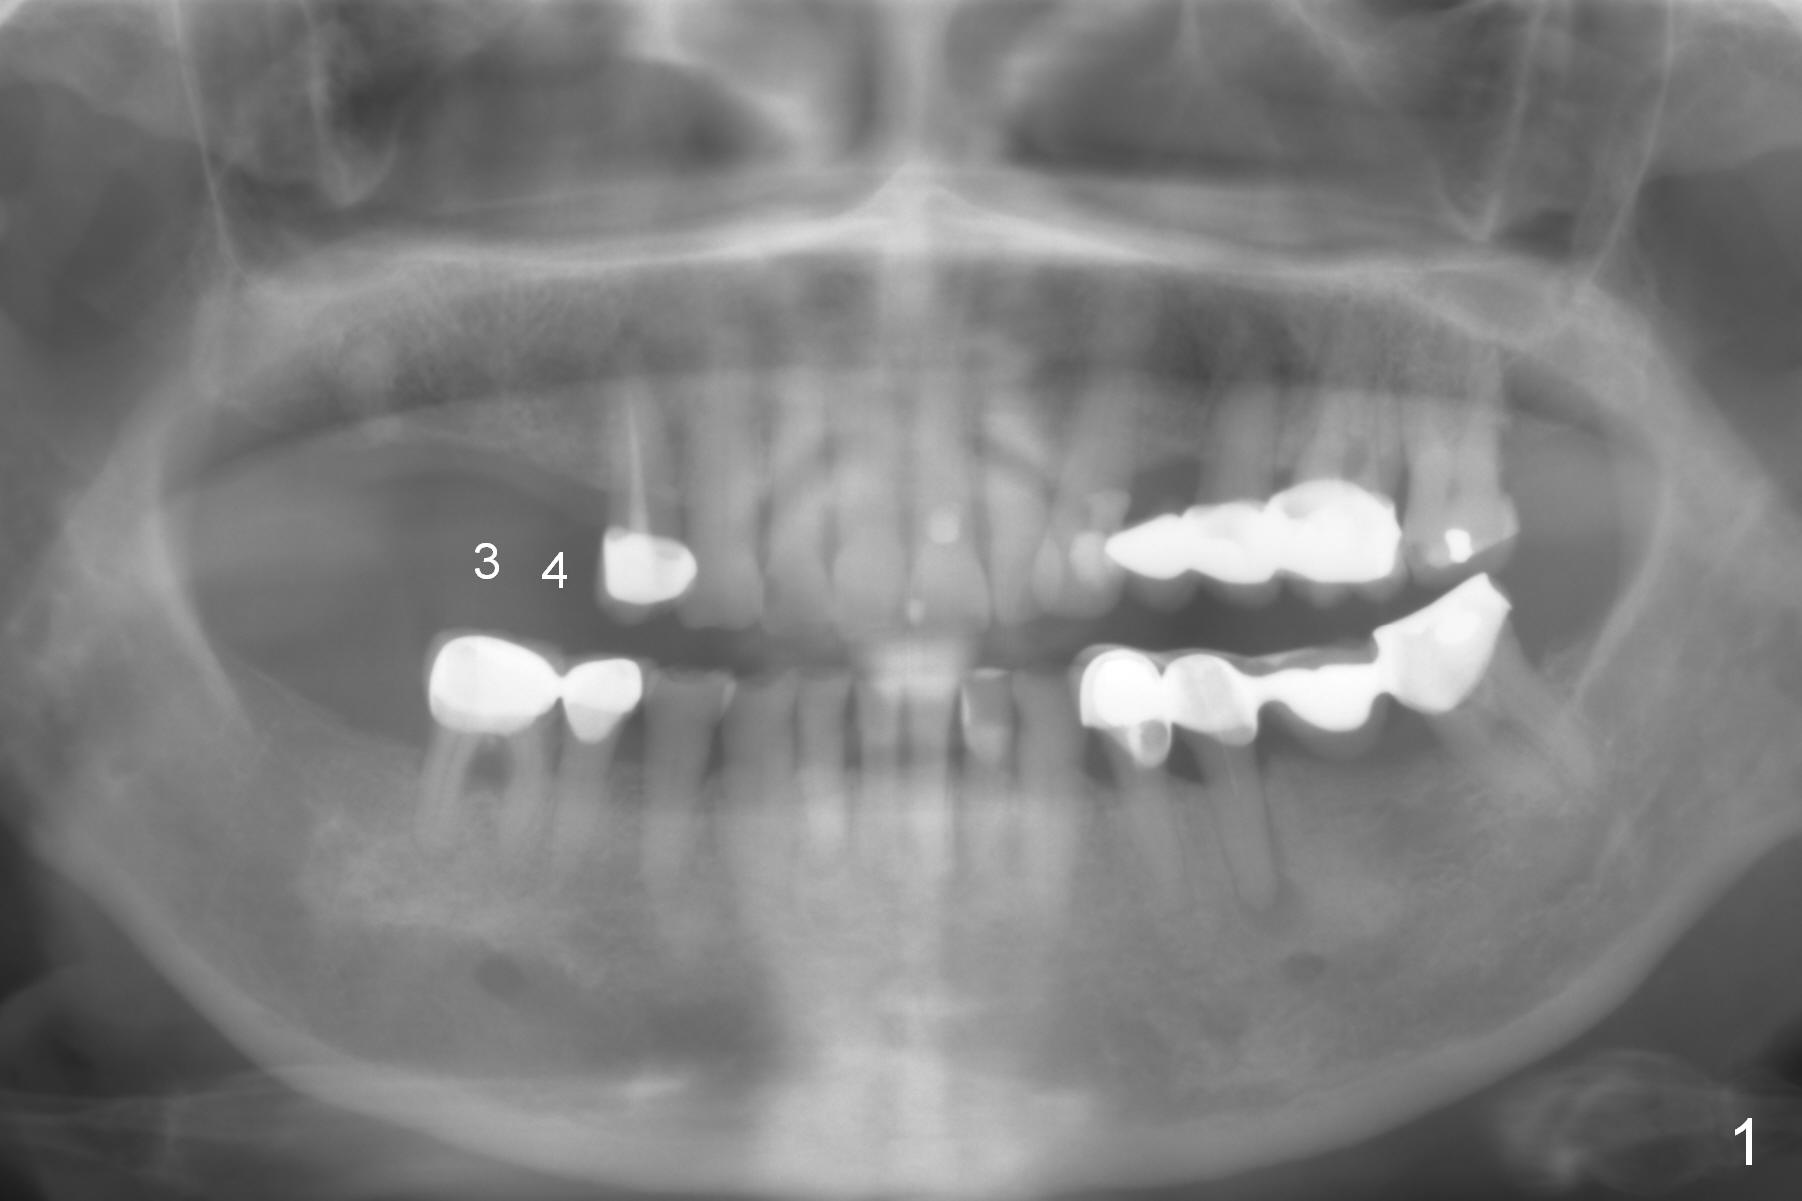

A 78-year-old woman (possible osteoporosis) has poor dentition and restoration (Fig.1). Implants will be placed at the sites of #3 and 4 with sufficient bone height as well as long edentulous vertical height (Fig.2). To improve implant/crown ratio and assure primary stability, long implants will be placed: 16 mm bone-level. Osteotomy is to be initiated through surgical stent with the longest Tatum 1.5 mm pilot drill, followed by incision, initial depth of 12 mm and PA. If the bone proves to be soft, use DIO bone expansion kit and wheel splitter . Splinted immediate provisional is going to be fabricated. Surgical stents are available.